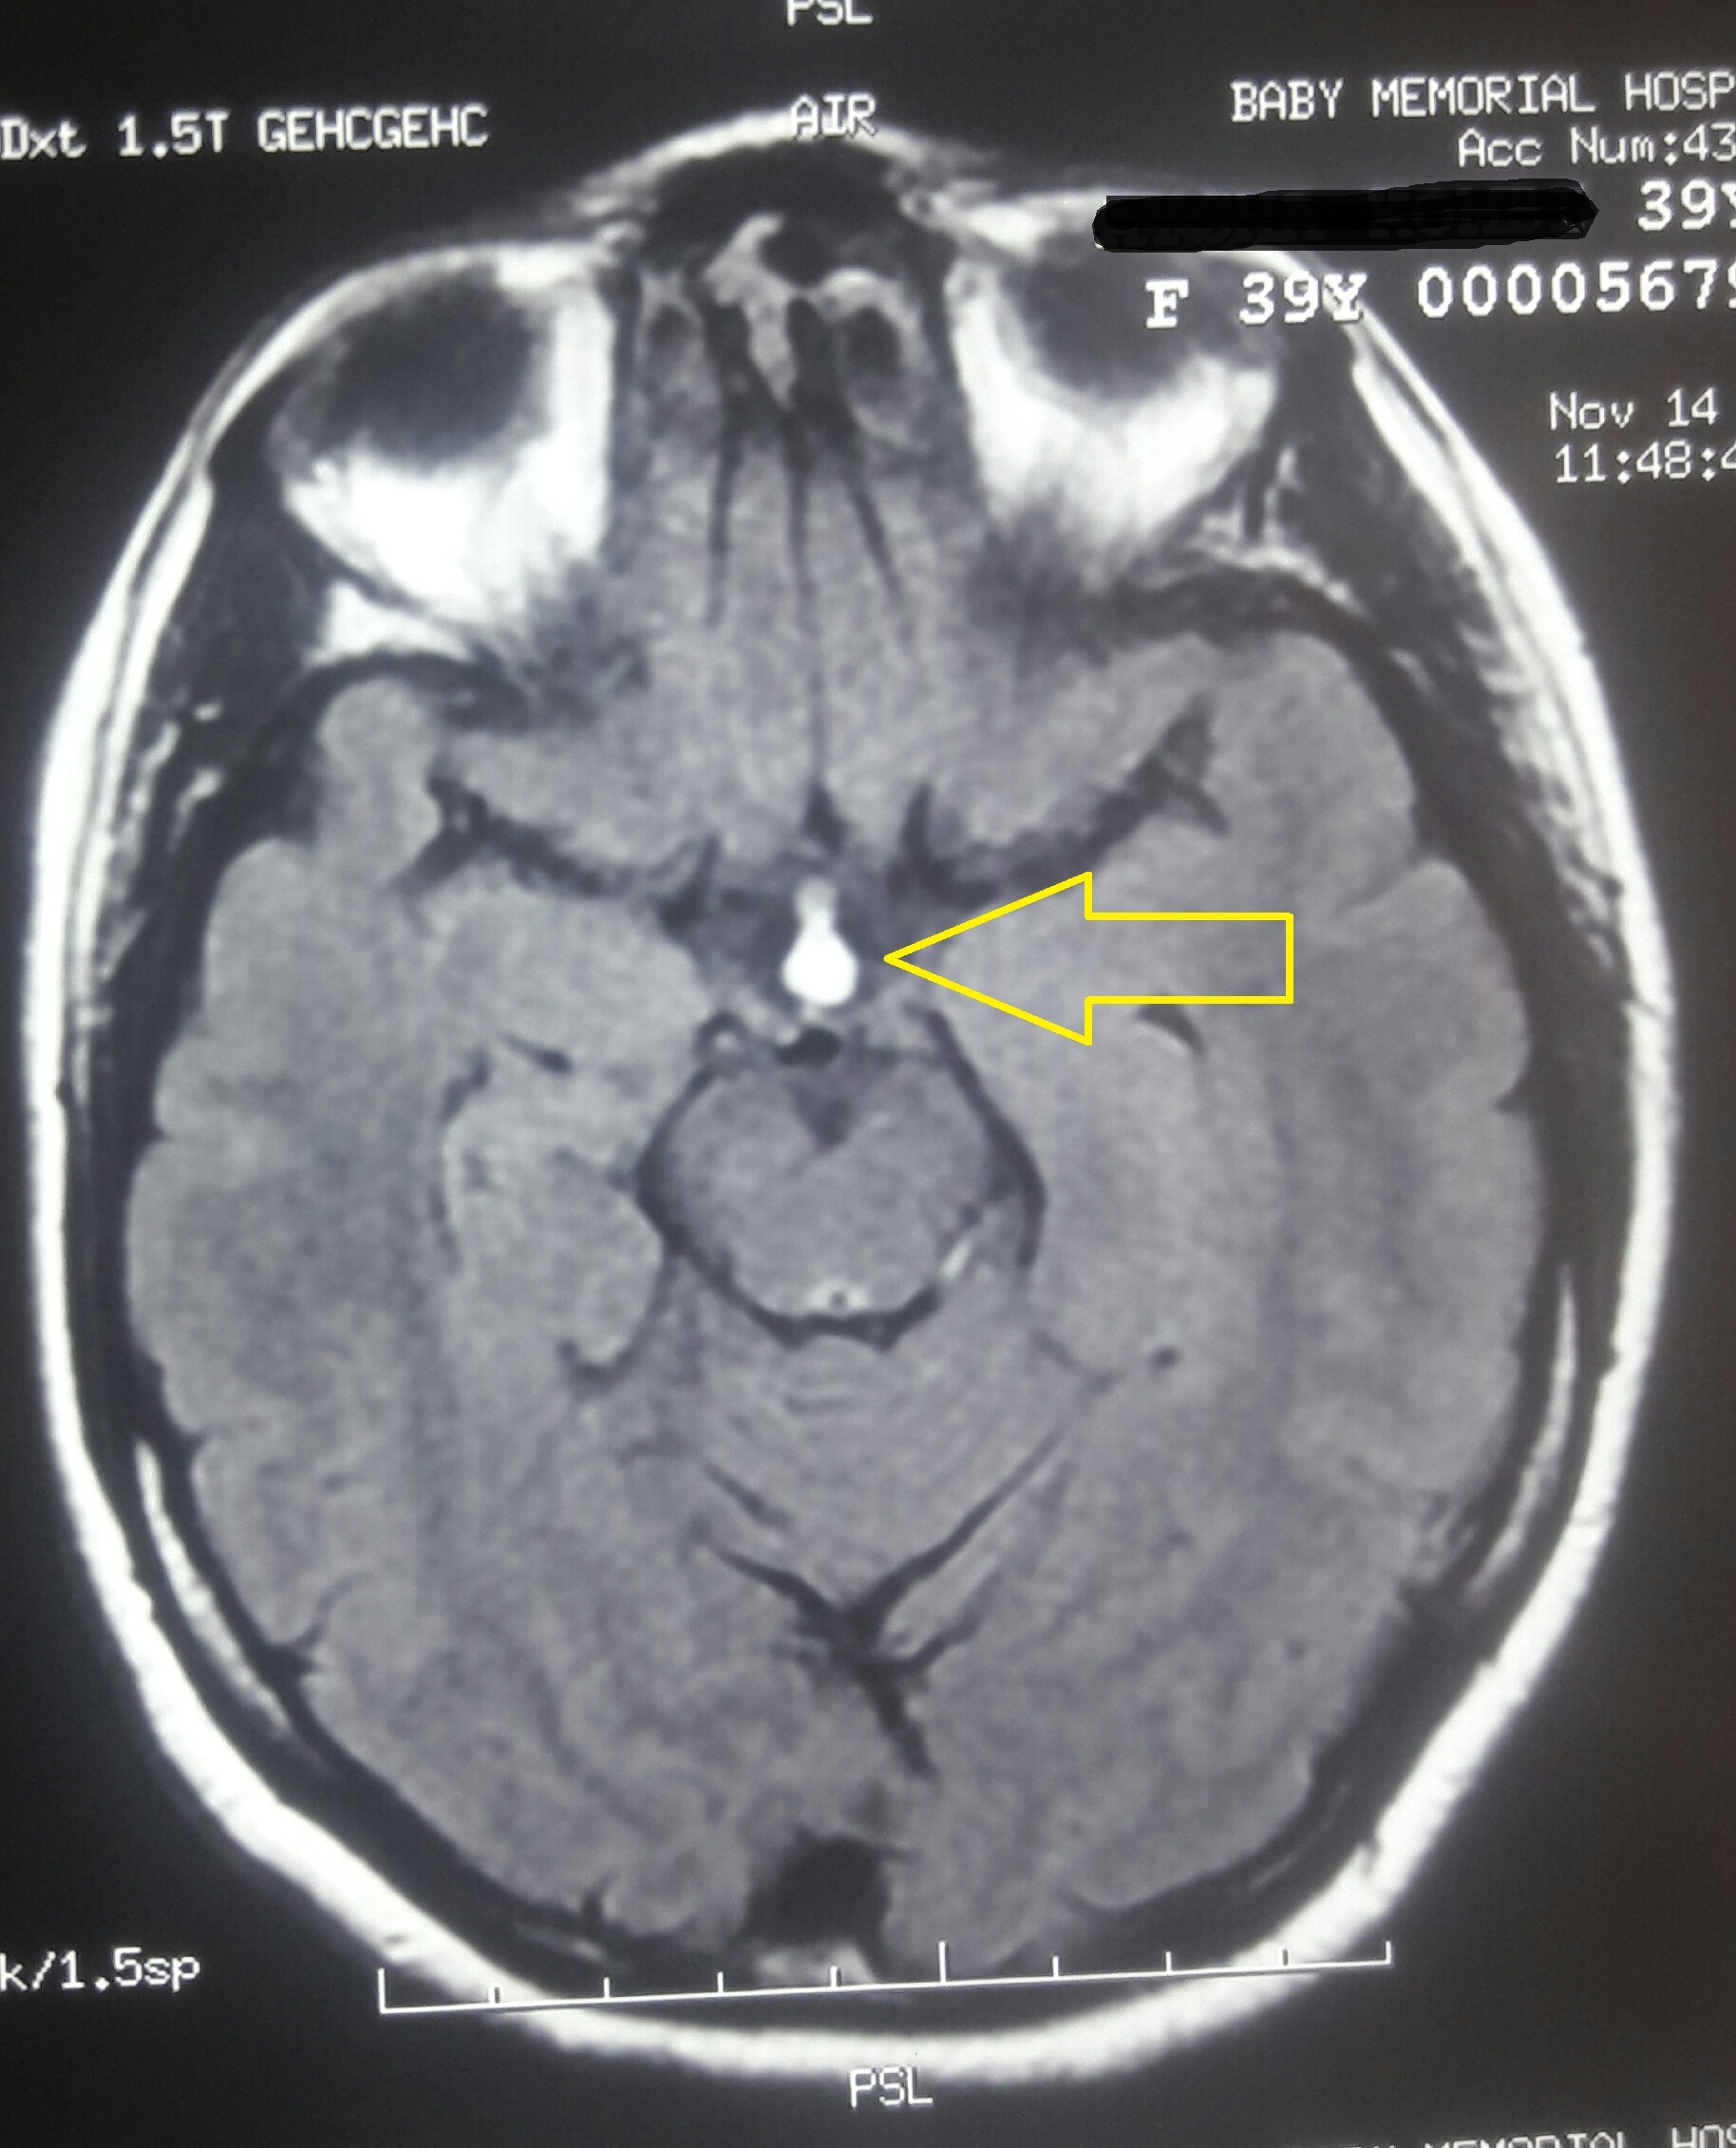

Tuber cinereum lipoma

Intracranial lipomas, Tuber cinereum, Intracranial tumoursAbstract